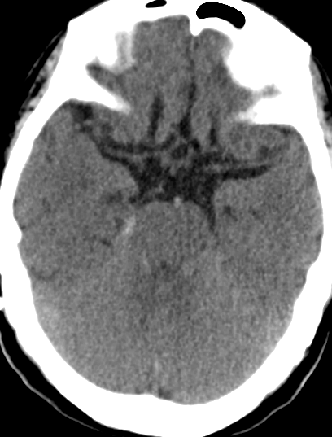

2013-8-2 CT

腰穿脑压240